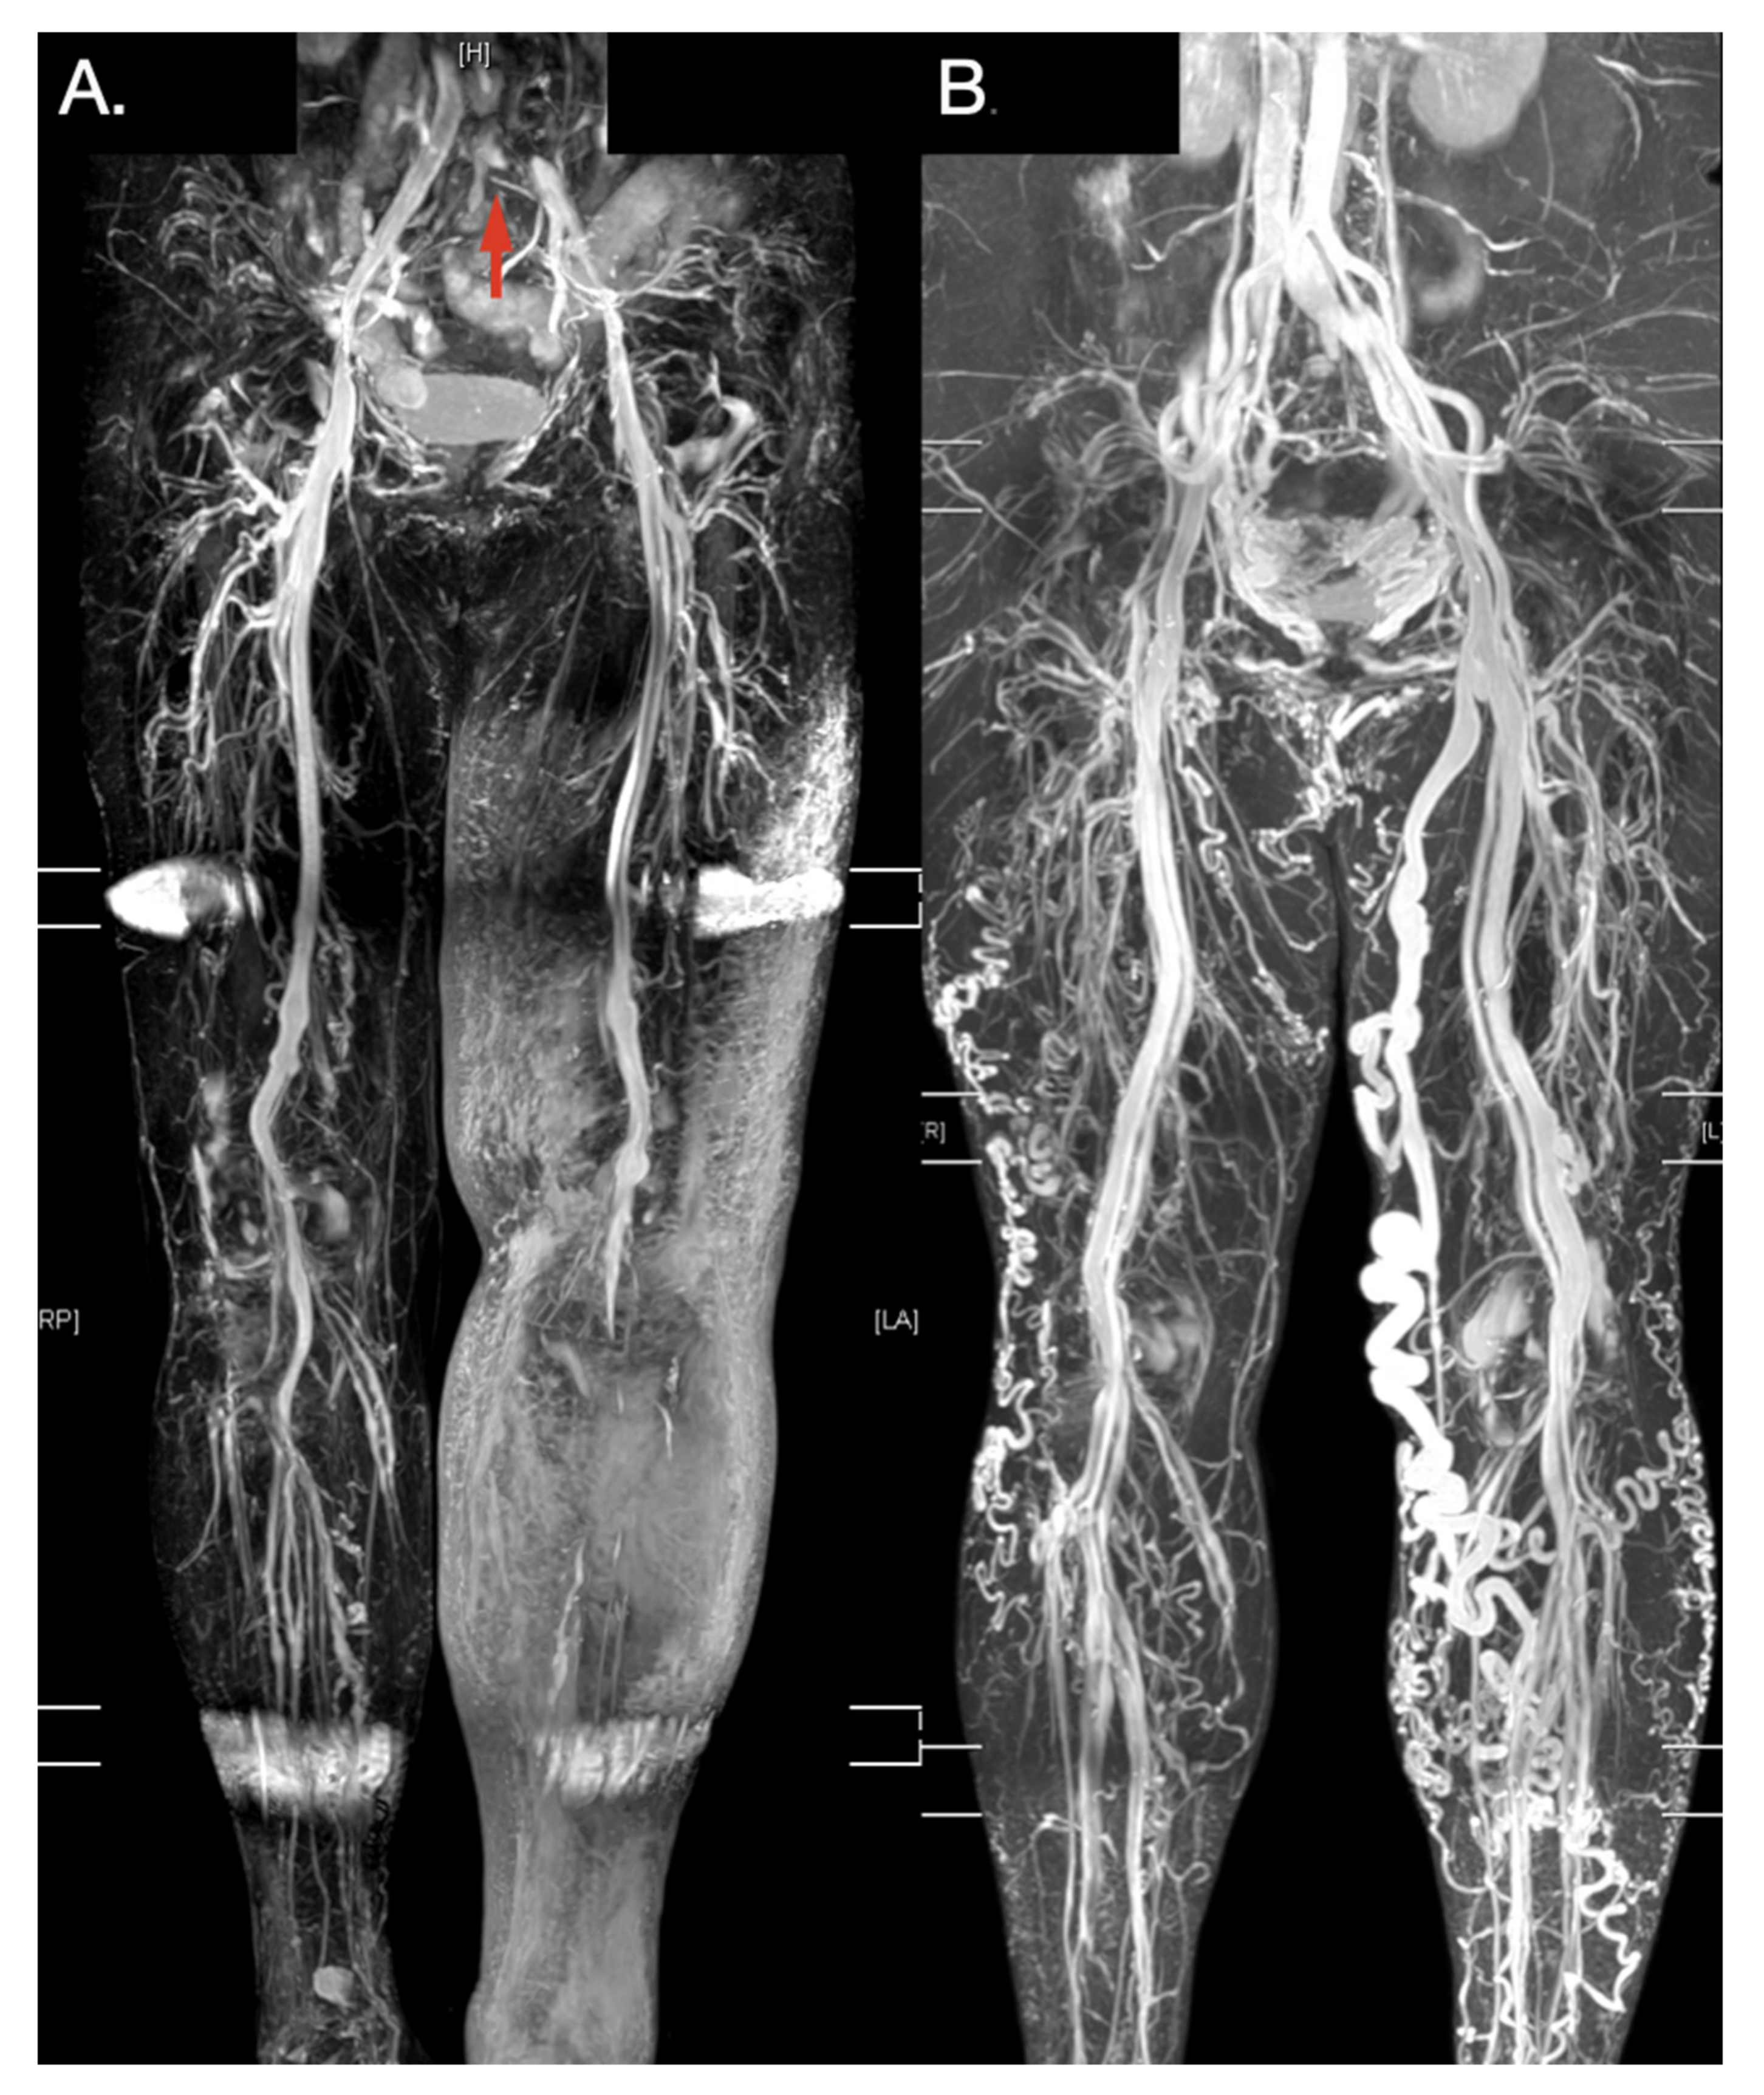

Figure 5. Typical TRANCE MR imaging of obstructive and varicose venous disease. (A) Left limb extended subcutaneous edema with a compressed left external iliac vein (Red arrow). (B) Lady with left great saphenous varicose vein. Her right thigh received truncal ablation of the right great saphenous vein 4 years ago.

Traditional contrastless MRA, such as TOF MRA and PC MRA, remain time-consuming for imaging the complete vascular structures of the lower extremities. Electrocardiographically gated, multi-step TSE techniques (e.g., TRANCE MRI) offer the possibility of imaging complete vascular structures of the lower extremities in clinical practice. Electrocardiogram gating helps researchers to adapt imaging times to different flow characteristics and, therefore, optimize the image quality more quickly. Although some studies have examined non-contrast-enhanced MRA, most studies have used this technique to evaluate arterial diseases [30,31,32,33,34]. Our study is innovative in that a TRANCE MRI was used investigate the management of complicated lower venous diseases [4,5,6,9]. The examination time may be shortened to less than 30 min by experienced radiological teams (Supplementary Video S1). The morphology of the venous anatomy of the lower extremities was clearly imaged in 3D without the use of a contrast media or radiation (Figure 5).